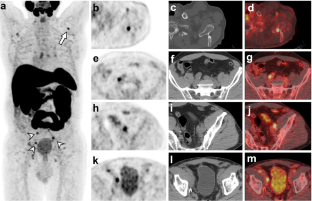

18F-PSMA-1007 PET/CT was positive in 24/40 patients, which yielded overall detection rate of 60%. Detection rate was 39%, 55% and 100% for PSA < 0.5, 0.5 to <1.0 and 1.0 to ≤2.0 ng/ml, respectively. PET/CT showed metastases in locoregional lymph nodes in 55% of patients, bones in 36% of patients and local recurrence in 9% of patients. Detection rate was correlated with PSA—a 0.1 ng/ml rise in PSA level increased odds for positive PET/CT by ~30%. PET/CT positivity was independent of GS and T stage. Verification of 40 lesions yielded sensitivity, specificity, PPV and NPV of 100%, 94.4%, 66.7% and 100%, respectively.